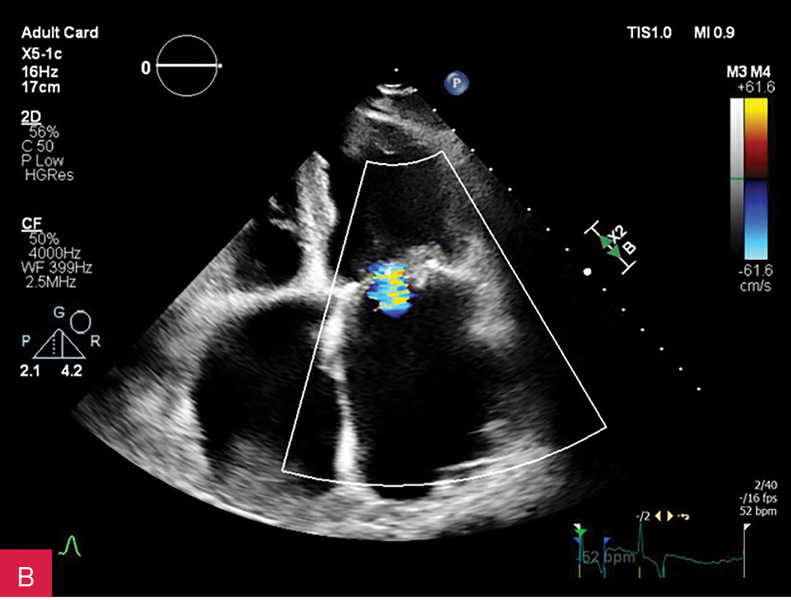

Rycina 3A-C. Badanie echokardiograficzne przezklatkowe (TTE) w osi krótkiej przymostkowej na różnych poziomach – płatków zastawki mitralnej (A), strun ścięgnistych (B) i mięśni brodawkowatych (C) – obrazuje owalną zmianę guzowatą, o dużych rozmiarach i nierównej echogeniczności, z widocznym wzmocnieniem brzeżnym